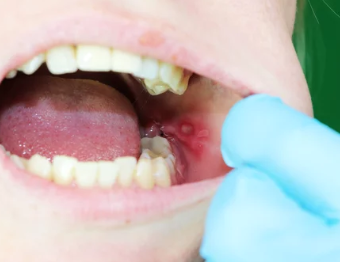

입안이 자주 헐고 아프다면 단순히 피곤해서 생긴 문제로 넘기기 쉬우나,

지속적으로 반복되거나 통증이 심한 경우, 면역력 저하, 영양 결핍, 만성질환의 신호일 수 있습니다.

‘구내염’ 또는 ‘아프타성 궤양’이라고도 불리는 이 증상은 입속 점막의 염증으로 인한 상처로,

작지만 식사, 대화, 양치질 등 일상생활에 큰 불편을 주는 증상입니다.